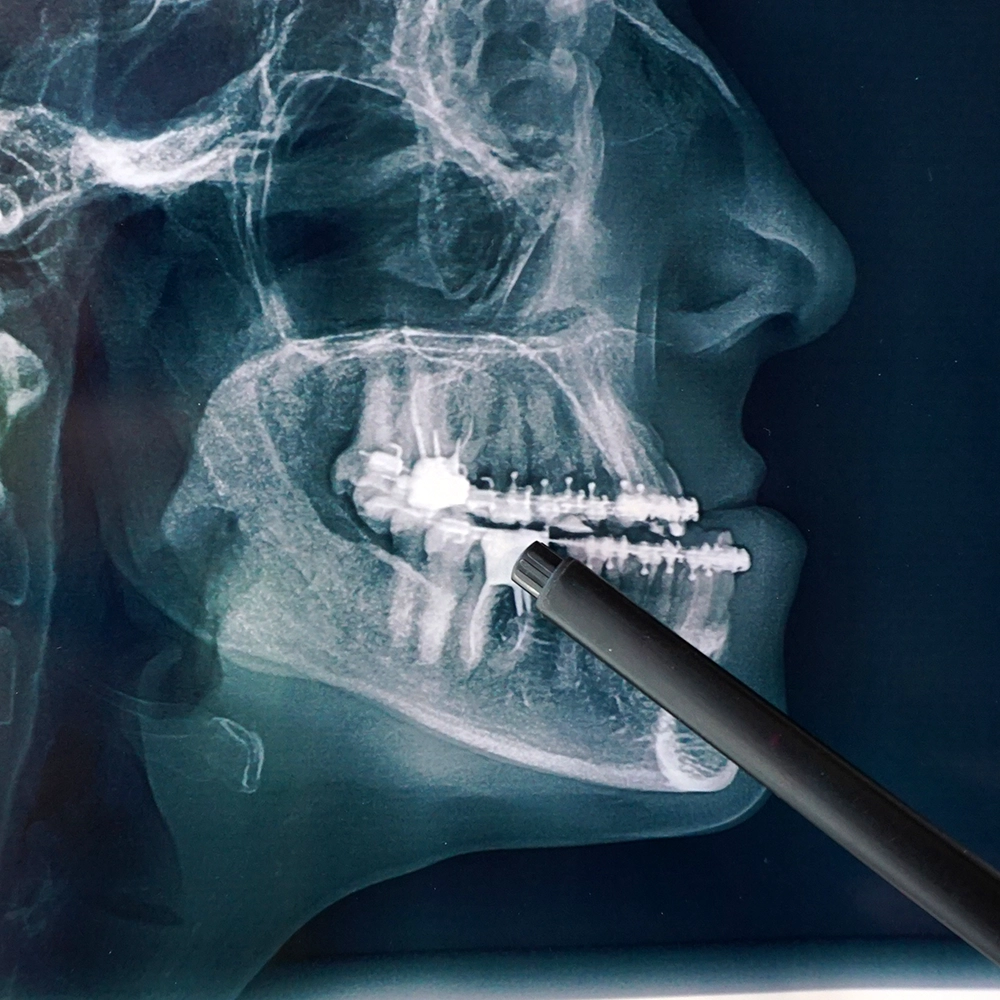

Misaligned jaws can make everyday activities like eating feel frustrating and uncomfortable. Patients may struggle to chew effectively, which can lead to digestive issues and lower quality of life. Corrective jaw surgery restores proper alignment, making eating more comfortable and enjoyable. Choosing Maine Oral Surgery & Dental Implant Center gives you the opportunity to reclaim functional oral health and confidence during meals.